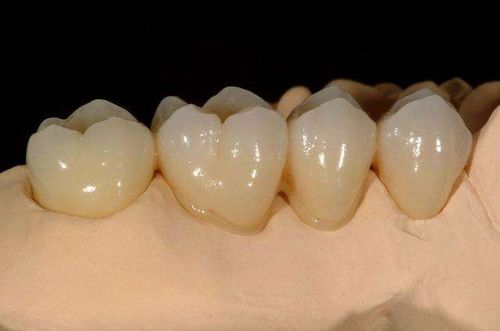

烤瓷牙是怎么回事 烤瓷牙是将瓷粉经过高温烧烤而成的全冠修复体。现多以金属为基底层,在它上面堆以烤瓷粉,再经过高温烧烤,烤瓷粉与金属紧密结合,形成金属陶瓷相结合的全冠修复体。... 烤瓷牙 充向雪 576 2023-12-26

前牙缺损修复体的设计是什么样的 牙体缺损有不同的情况,其修复体的设计也不同。前牙区因涉及美观,所以多采用美学修复体,如烤瓷冠、全瓷冠和瓷贴面等修复形式。缺损多因龋病或外伤引起。根据不同的缺损范... 牙齿治疗 丰尔槐 1286 2024-02-23